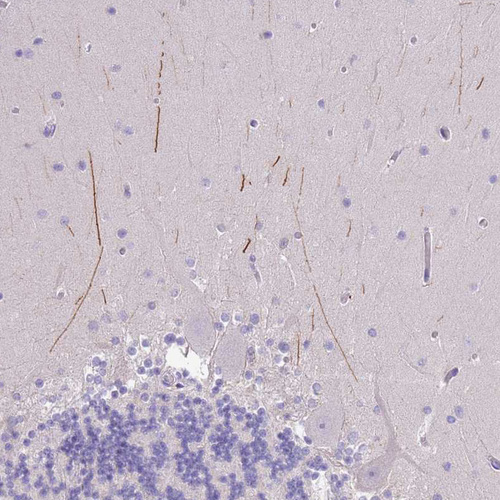

Immunohistochemical staining of human cerebellum shows moderate positivity in processes.